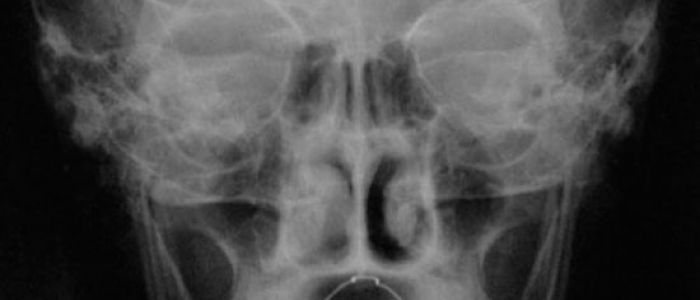

Radiografías Extraorales

Las radiografías extraorales se emplean cuando no es factible obtener información diagnóstica adecuada en las series de radiografías intraorales, es así que son utilizadas para observar un área grande de los maxilares y del cráneo en una sola radiografía. Los exámenes radiográficos extrabucales tienen el propósito de evaluar áreas grandes del cráneo, dientes impactados y patrones de erupción, crecimiento y desarrollo; examinar la extensión de lesiones grandes, traumatismos, articulación temporomandibular. Son de mucha utilidad principalmente en Ortodoncia y Cirugía Bucal.

Existen varias radiografías extraorales entre las cuales se tiene: